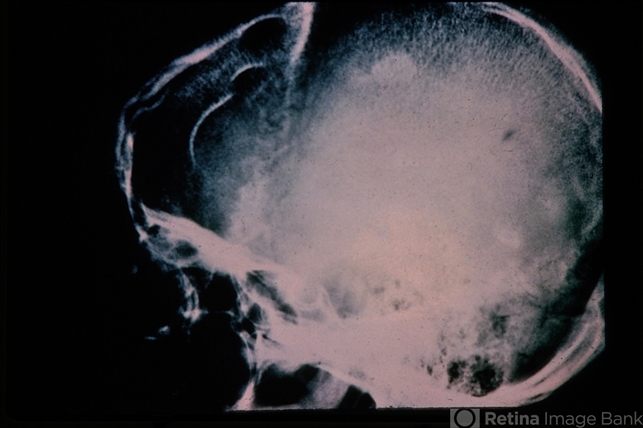

- Tuberous Sclerosis- skull X-ray showing intracranial calcification.